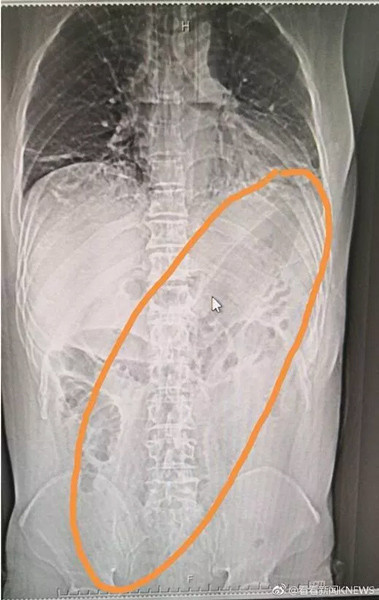

Çin, son yılların en şaşırtıcı tıbbi olayını konuşuyor. Çin'de ismi açıklanmayan hasta geçtiğimiz hafta mide bulantısı ve karın ağrısı şikayetiyle hastaneye gitti. Röntgeni çekilen adamın anüsünden 30 santimetrelik patlıcan çıktı.

HASTALIĞI İÇİN YAPMIŞ; Yapılan incelemeler ve röntgen sonuçlarına bakarak adama soru soran doktorlar aldıkları yanıtla iyice şaşkına döndü. Acı içinde kıvranan adam sindirim ve boşaltım sorununu ortaya kaldırmak için anüsünden 30 santimetre uzunluğundaki bir patlıcan soktuğunu ve bunun 2 gündür içinde sıkıştığını söyledi.